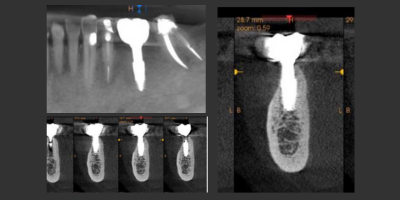

Un evento formativo di valore con un’agenda molto fitta incentrata alla spiegazione dettagliata delle regole chirurgiche e protesiche relative alla riabilitazione avvitata e cementata su impianti a connessione conica con o senza one abutment one time technique e all’utilizzo di polveri non abrasive e punte piezo ceramiche in peek e carbonio seguendo gli step della GBT con o senza coadiuvanti topici.